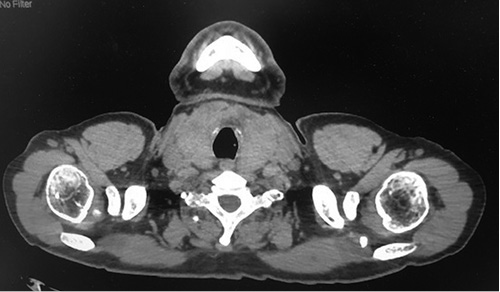

3. Fig. 3. MSCT of the chest in cross section. | |

| Subject | ||

| Type | Other | |

View

(37KB)

|

Indexing metadata ▾ | |